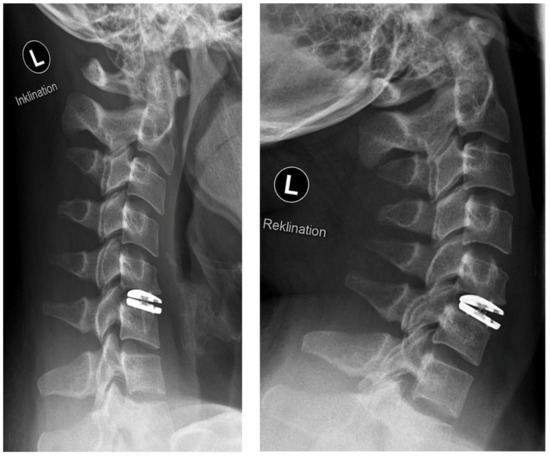

Figure 3.

Postoperative radiographs in flexion (“Inklination”) and extension (“Reklination”).